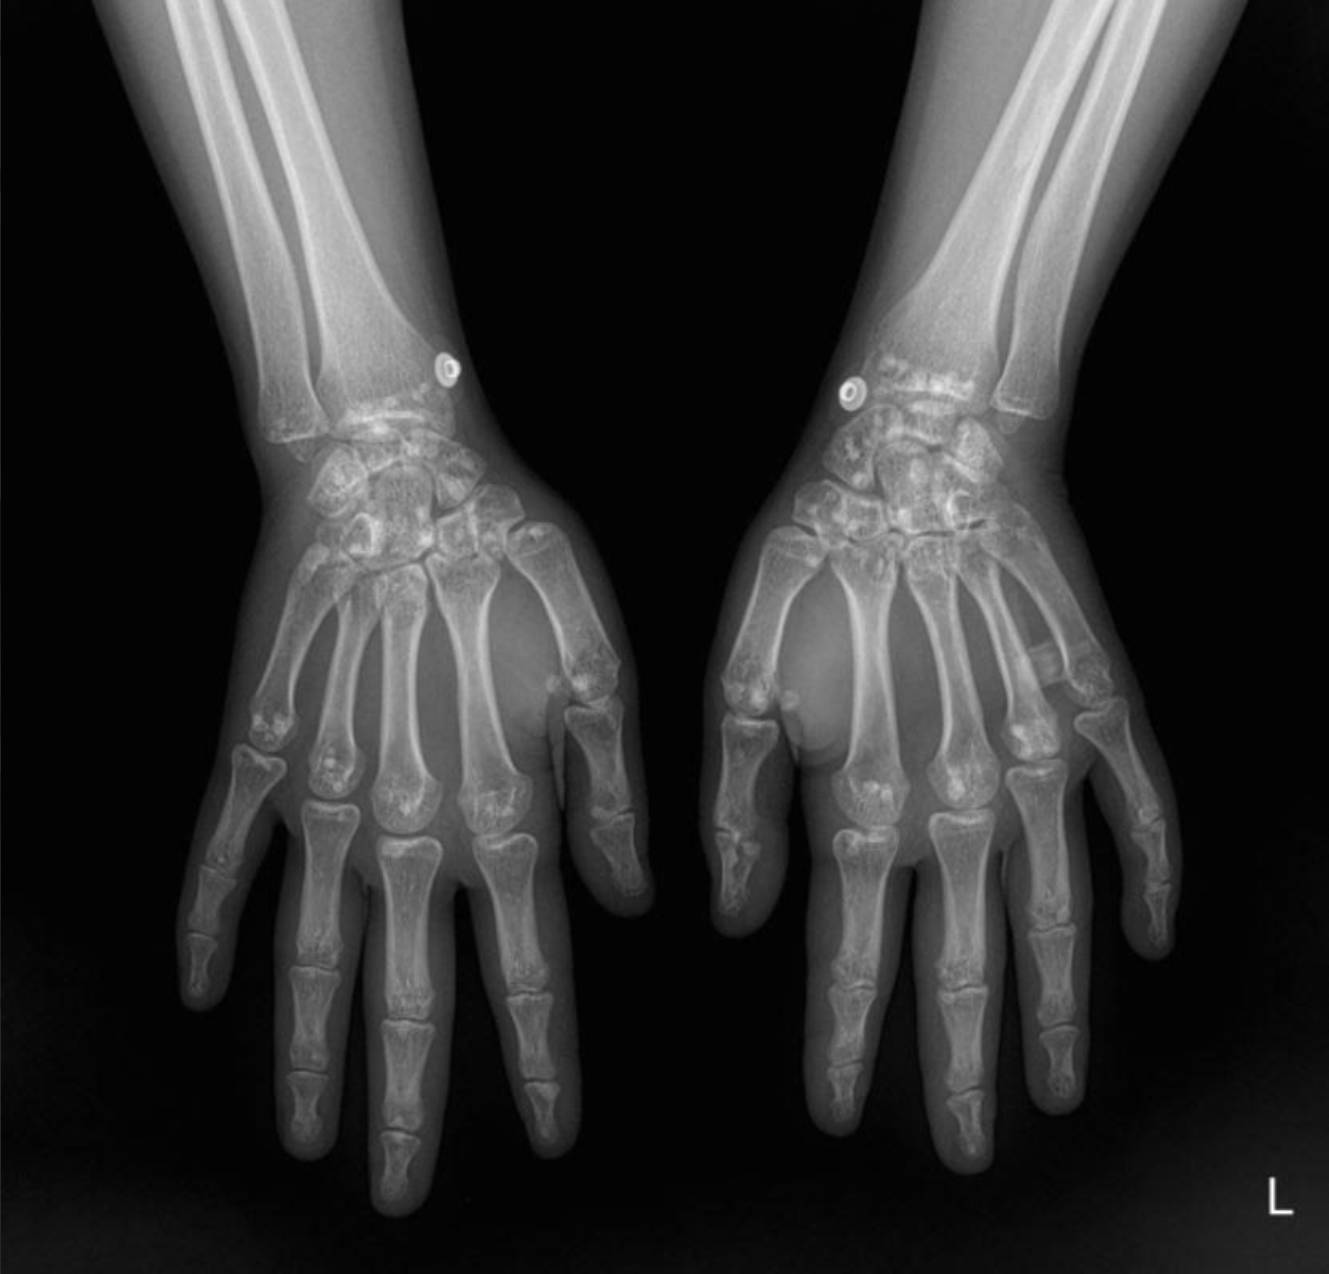

Radiological Findings: Skeletal X-rays (Incidental Discovery)

During the extensive workup for her hypertension and renal issues, skeletal X-rays were performed, which revealed a striking and unexpected finding.

The X-rays of the pelvis, knees, elbows, wrists, and ankles demonstrate multiple, discrete, well-circumscribed sclerotic (densely opaque) lesions distributed symmetrically throughout the bones. These lesions are typically ovoid or spherical, varying in size, and are predominantly located in the epiphyses and metaphyses of long bones, as well as in the carpal and tarsal bones and the pelvic girdle.

Specifically:

- Wrists and Hands: The carpal bones, distal radius and ulna, and to a lesser extent, the metacarpals and phalanges, exhibit multiple small, dense foci.

These widespread, symmetrically distributed sclerotic bone islands are pathognomonic for hereditary osteopoikilosis (also known as osteopathia condensans disseminata). This condition is typically benign and often discovered incidentally. While not directly related to her renal artery stenosis or hypertension, its discovery is crucial for patient management as it can sometimes be associated with other connective tissue disorders, though often it is an isolated finding.